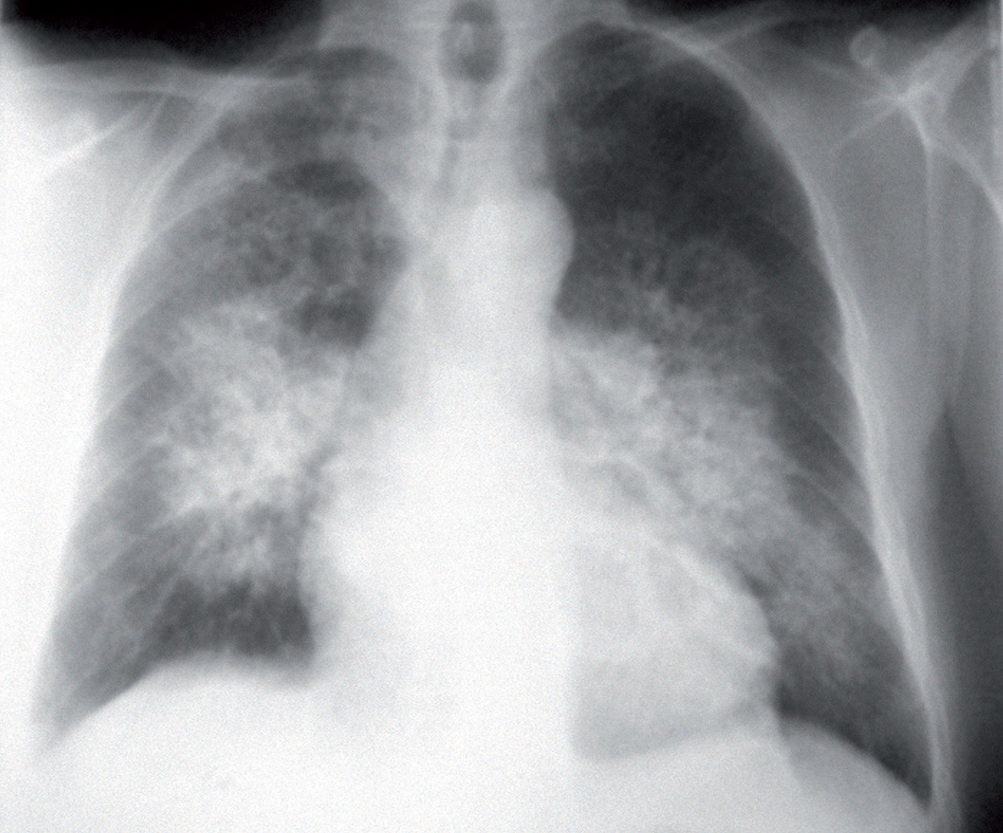

Si notino i segni di ridistribuzione vascolare verso i campi superiori e l’ingrandimento secondario alla congestione di entrambi gli ili polmonari definito “ad ali di farfalla”.

La radiografia del torace può mostrare segni di congestione interstiziale (linee di Kerley B), l’edema alveolare ad “ali di farfalla” e quote di versamento pleurico bilaterale.